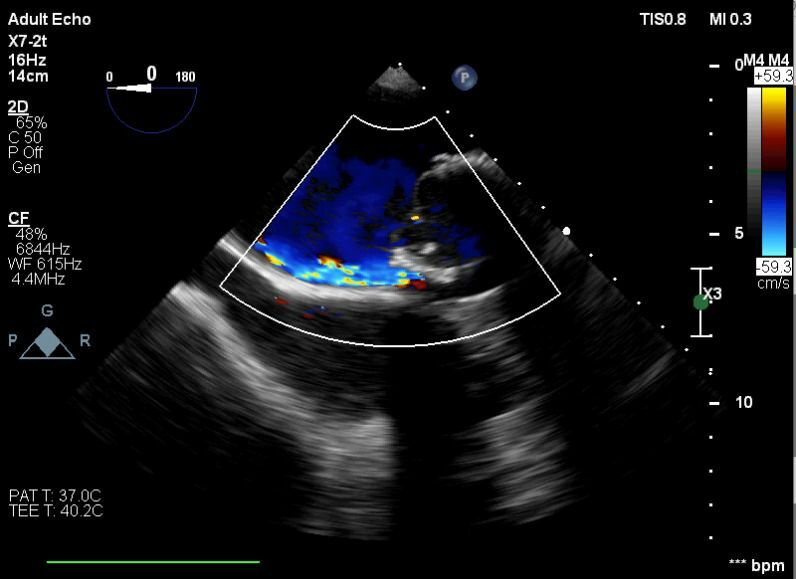

Hastanede yapılan, “Balıkesir’de ilk” nitelikli işlemlerin bir yenisi de Kardiyoloji Anabilim Dalı bünyesinde girişimsel kardiyoloji ile gerçekleştirilen paravalvüler kaçak kapatılması işlemi oldu.

Yapılan işlemi gerçekleştiren ekipte yer alan Prof. Dr. Halil Kısacık, Doç. Dr. Eyüp Avcı, Doç. Dr. Tarık Yıldırım ve Doç. Dr. Özgen Şafak konu hakkında açıklamalarda bulundu. Daha önce kalp kapakçığı değişim ameliyatı olan hastada takılan kapağın kenarından ayrılmasıyla kan kaçağı (paravalvuler leak) meydana geldiğini belirten öğretim üyeleri, Kardiyoloji Anabilim Dalına başvuran hastaya, Türkiye’de sayılı kalp merkezinde yapılan ve önemli düzeyde cerrahi deneyim gerektiren paravalvüler kaçak kapatılması işlemi uygulandığını dile getirdi. İşlemin sadece girişimsel kardiyologlar tarafından yapıldığının altını çizen öğretim üyeleri, işlem sırasında hastanın kalbi durdurulmadan ve göğüs kafesi kesilmeden, kasığından girilerek yapay kalp kapağındaki kaçağın ameliyatsız kapatıldığını söyledi.